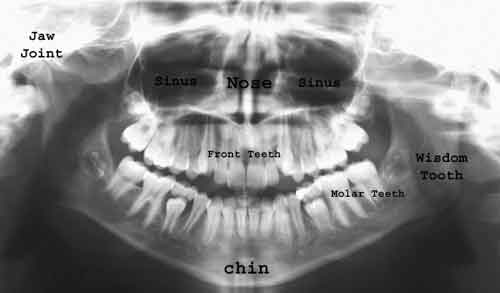

Ortopantomografia

Ortopantomografia PRINCIPII TEHNICE n Miscarea de rotatie tub-caseta n Miscarea de translatie a casetei in port-caseta Imagini “fantoma n Citeste tot ... 453 cuvinte

Dimensiune mica + cu imagini |